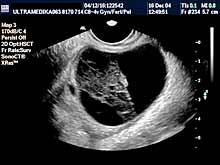

B) ULTRAZVUČNI PREGLED MALE KARLICE

Organi male karlice kod žena su: materica, jajnici, jajovodi,

spoljne genitalije, regionalne limfne žlezde.

Vrsta i sadržaj pregleda:

- Preporučeni pregled je sa vaginalnom sondom - bez

punjenja mokraćne bešike, izuzetno sa punom bešikom.

- 3D Sono CT - multiplanarna (u tri ravni) analiza volumena organa

male karlice. Ova tehnika podrazumeva i pregled površine materice i

jajnika, osim njihove unutrašnjosti.